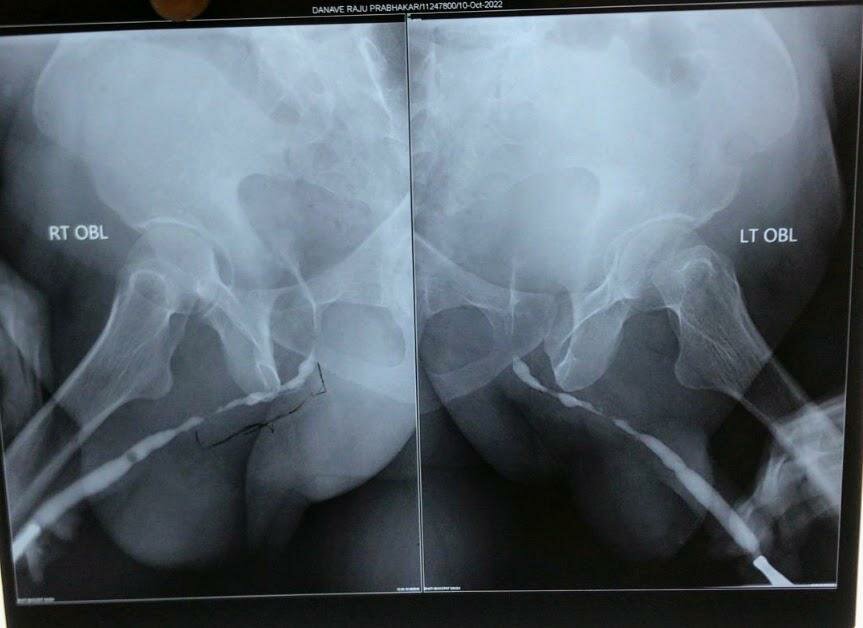

Long Segment Bullbar Urethral Stricture Treated by BMG Urethroplasty | Dr. Bhoopat Bhati

A 58 years old male was having difficulty in passing urine. He had underwent multiple endoscopic operation for stricture in urinary pipe in past. RGU ...